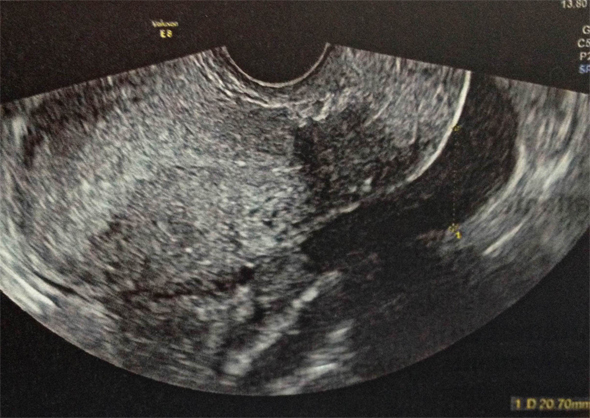

On évoque, en priorité les diagnostics d’urgence ( = diagnostics GRAVES ), donc GEU , la salpingite et la torsion d’annexe.

La GEU en priorité

Rappel : TOUTE FEMME EN AGE DE PROCREER PRESENTANT DES METRORRAGIES ET/OU DES DOULEURS PELVIENNES A UNE GEU JUSQU'A PREUVE DU CONTRAIRE